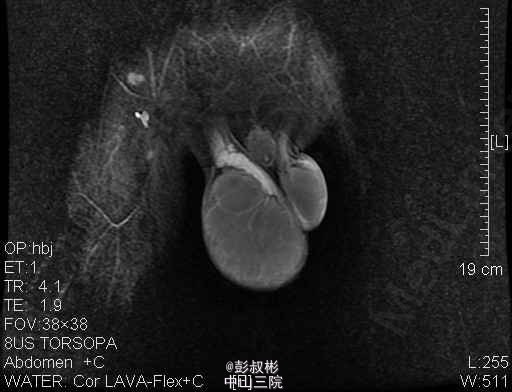

1、主诉:发现右侧睾丸肿大1年。 2、患者为青年男性,隐匿性起病。患者于一年前无明显诱因发现右侧睾丸变硬,并逐渐增大,无疼痛与牵引感,也不影响排尿和日常活动,未经任何诊治,近来自觉右侧睾丸钝痛,到我院门诊求诊,诊断为:"右侧睾丸肿瘤"。现为进一步诊治收入我科。起病以来,患者无寒战、发热,无恶心、呕吐、腹泻,食欲、精神、睡眠一般,大便正常,近期体重无明显下降。。 3、体格检查:双肾区无红肿、隆起,无叩痛,双侧肋脊点、肋腰点无压痛。腹平软,双侧输尿管走行区无压痛,膀胱区无膨隆,压痛阴性,双侧腹股沟区未触及肿物,阴毛呈男性分布,外生殖器发育正常,尿道外口未见异常,右侧阴囊内可触及右侧睾丸明显增大,约“20×10×8”cm大小,轻压痛,透光试验(-)。直肠指检:胸膝位,前列腺不大,质韧,中央沟存在,表面光滑,无结节,触痛阴性,指套未见沾血。 4、辅助检查:B超示:右侧睾丸肿瘤。盆腔MR平扫+增强扫描提示:右侧阴囊内占位,考虑睾丸来源恶性肿瘤,精原细胞瘤可能大。 5、诊疗措施:入院后予患者完善相关检查,三大常规及生化回报未见明显异常,未见明显手术禁忌症,考虑患者可耐受手术,拟予患者行右侧睾丸治疗根治性切除术。